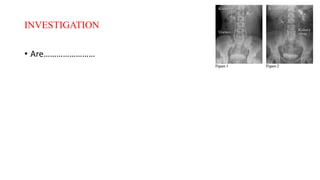

INVESTIGATION

• Are……………………